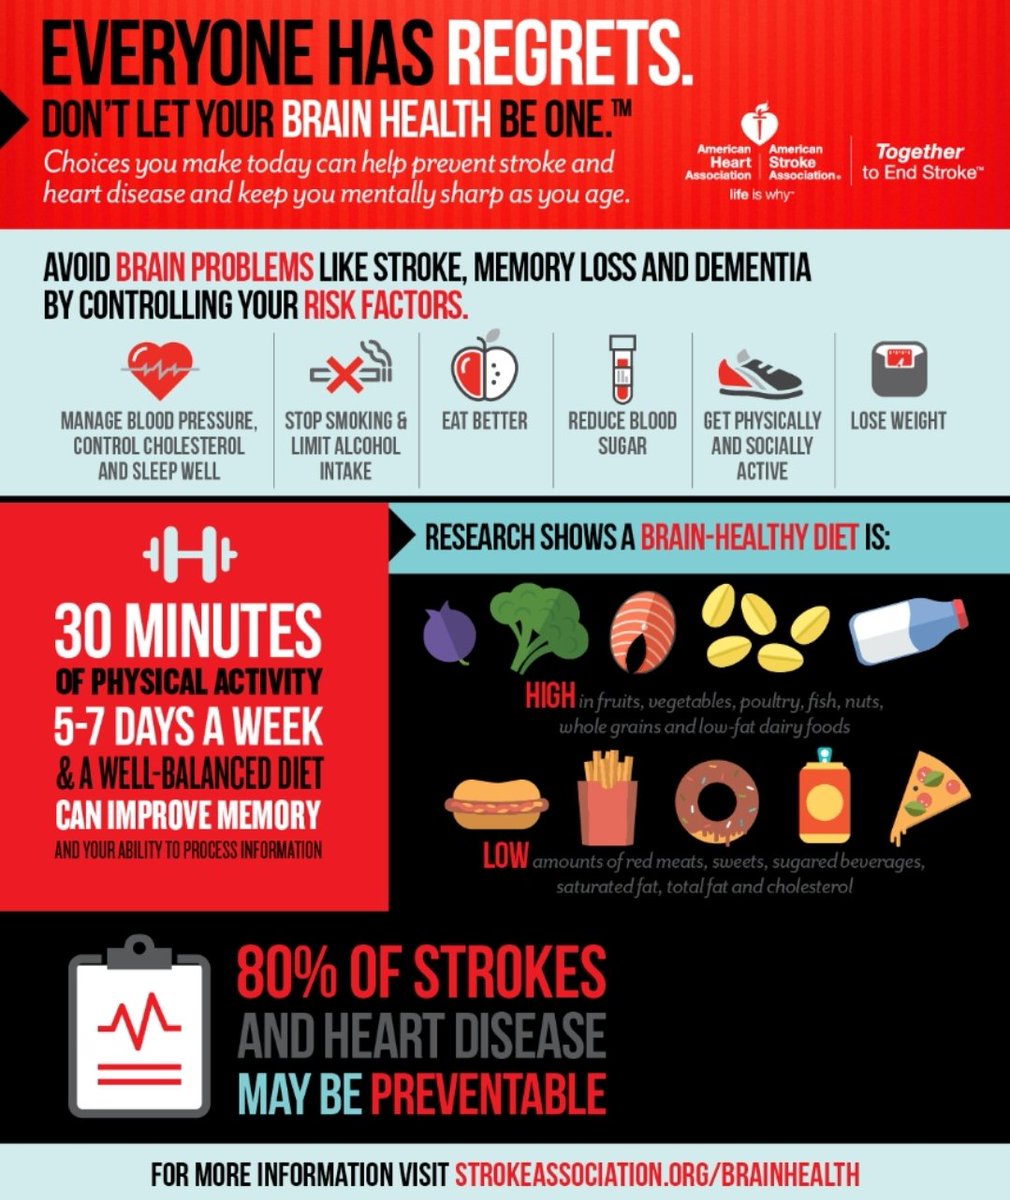

💥عوامل الخطورة

🧠ارتفاع الضغط

🧠السكري

🧠الكوليسترول

🧠التدخين

🧠قلة النشاط البدني

🧠أمراض القلب

❤ارتجاف اذيني❤تخثرات

❤الصمامات❤عيوب خلقيه

💥أخرى

🧠امراض الشرايين المغذيه للمخ

🧠الحوادث وطقطقة الرقبه

🧠المخدرات

🧠أمراض الدم

🧠أمراض وراثيةومناعيه